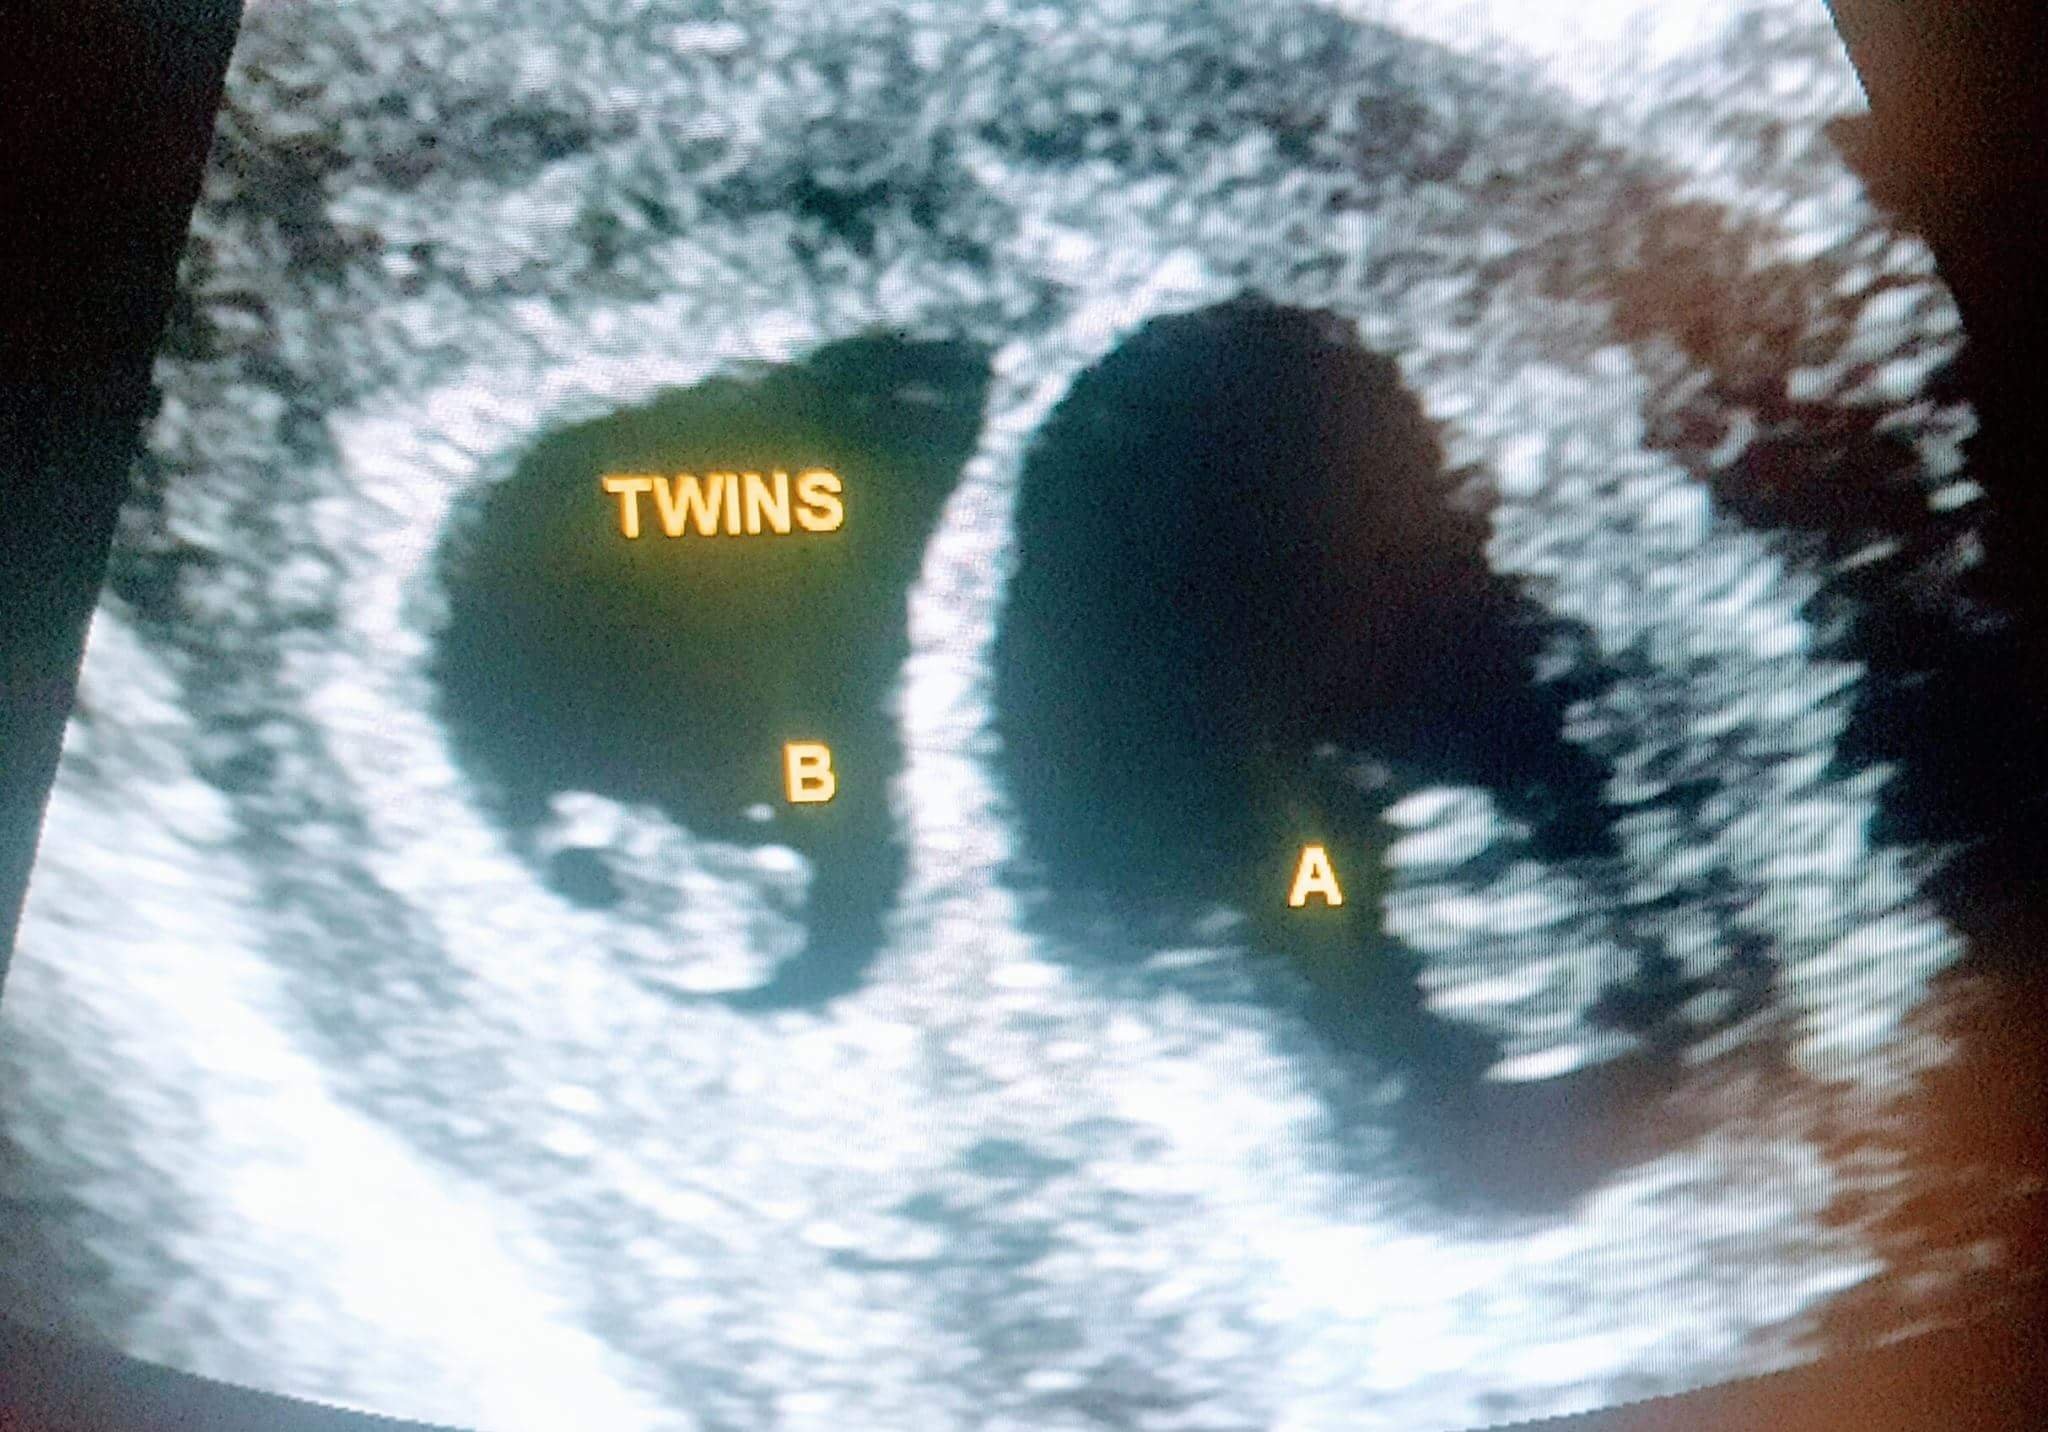

Im sure there's already a post about this but I want to talk with some ladies who are also expecting multiples. Have you started showing yet? I'm just always so scared because it's a high risk pregnancy. When is your EDD? Ahhhhh I'm just going crazy here and can't sleep so I'd love to hear from you ladies! Oh I'm ten weeks BTW. I'll post my US from six weeks below.